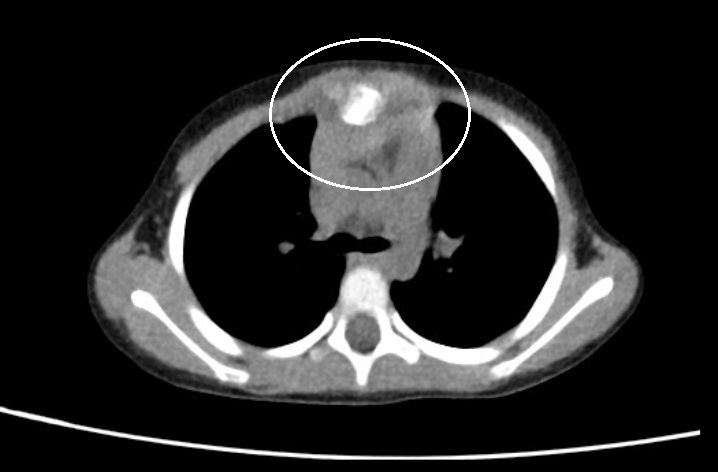

入院查体:前胸壁正中隆起,具有有明显压痛,胸骨局部活动。X线检查提示胸骨角与胸骨体之间骨折。局部骨骼与胸骨体成角。胸壁骨骼三维重建提示胸骨局部离断,离断部位为胸骨体上段。术前诊断为继发性胸廓畸形,胸骨粉碎性骨折。经充分术前准备,今日上午实施手术治疗。术中采用正中切口,游离胸骨。术中见胸骨角下方胸骨离断,离断长度约1CM,与胸骨体完全分离,局部无明显活性。将离断胸骨部分清除,以MatrixRIB重建胸骨。术野留置引流管,关闭切口,手术结束。

(CT提示胸骨局部病变)